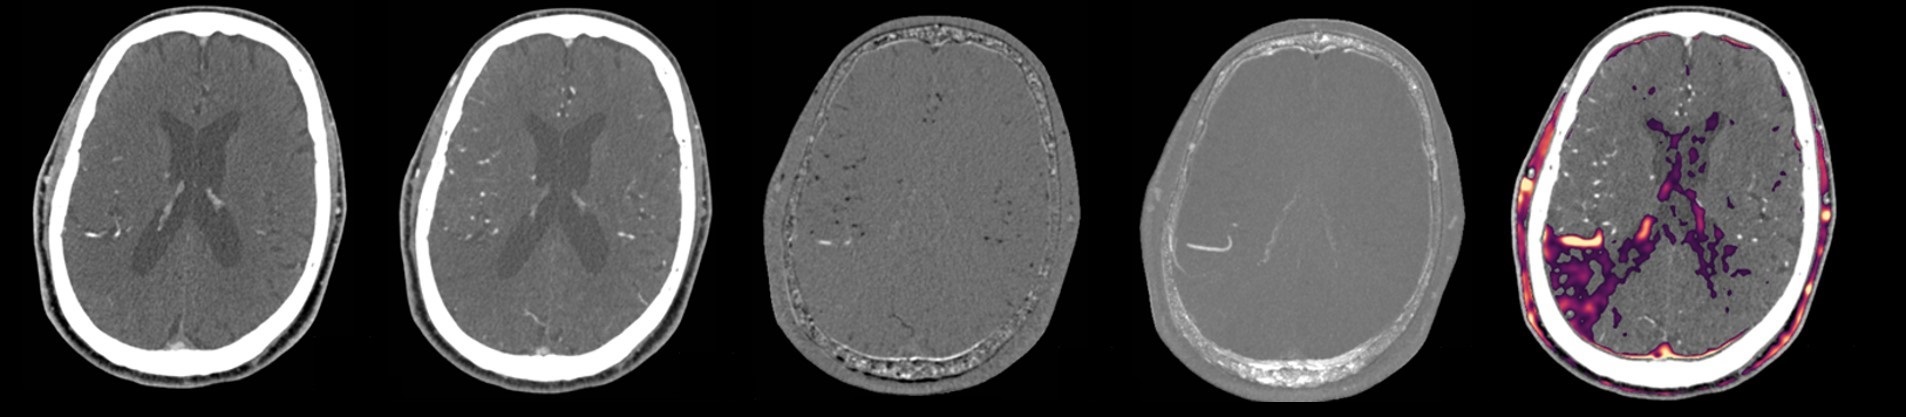

Recalage et soustraction digitale

L’ajout d’une seconde acquisition artériographique, en plus de distinguer certains phénomènes imitant l’occlusion et d’augmenter la sensibilité globale, permet une nouvelle possibilité de post-traitement. La soustraction digitale du volume de la phase artérielle précoce à celui de la phase artérielle tardive permet une cartographie efficace des zones de retard perfusionnel.

Bien que les zones identifiées ne correspondent pas avec certitude à un territoire ischémique ou de pénombre, elles apportent une information similaire à l’imagerie perfusionnelle, bien que temporellement moins précise, sans compromettre le détail anatomique.

Un recalage des volumes angioscanographiques est nécessaire pour compenser le mouvement du patient entre les acquisitions. Nous avons développé un algorithme de recalage rapide intégré au calcul de soustraction des phases, sur une plateforme indépendante et mobile. Une solution de post-traitement qui sera disponible gratuitement aux centres participants est en cours de développement.